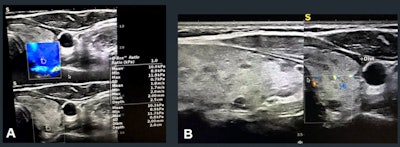

The study included 200 total thyroid nodules, assessed by conventional sonography to gather TI-RADS scores and important characteristics. The investigators used a 7.5 MHz probe to assess vascularity pattern and resistive index, performed quantitative elastography evaluations via color mapping, and calculated average and maximum velocities. They confirmed final diagnoses of all thyroid nodules via histopathology assessment or follow-up imaging.

The study found 37 TI-RADS 4 nodules, 15 of which were malignant, and 57 TI-RADS 5 nodules, 12 of which were malignant.

Overall, area under the curve (AUC) for TI-RADS assessment was 0.76. Adding elastography and resistive index measures to the mix translated to higher AUC values for TI-RADS 4 and 5 nodules.